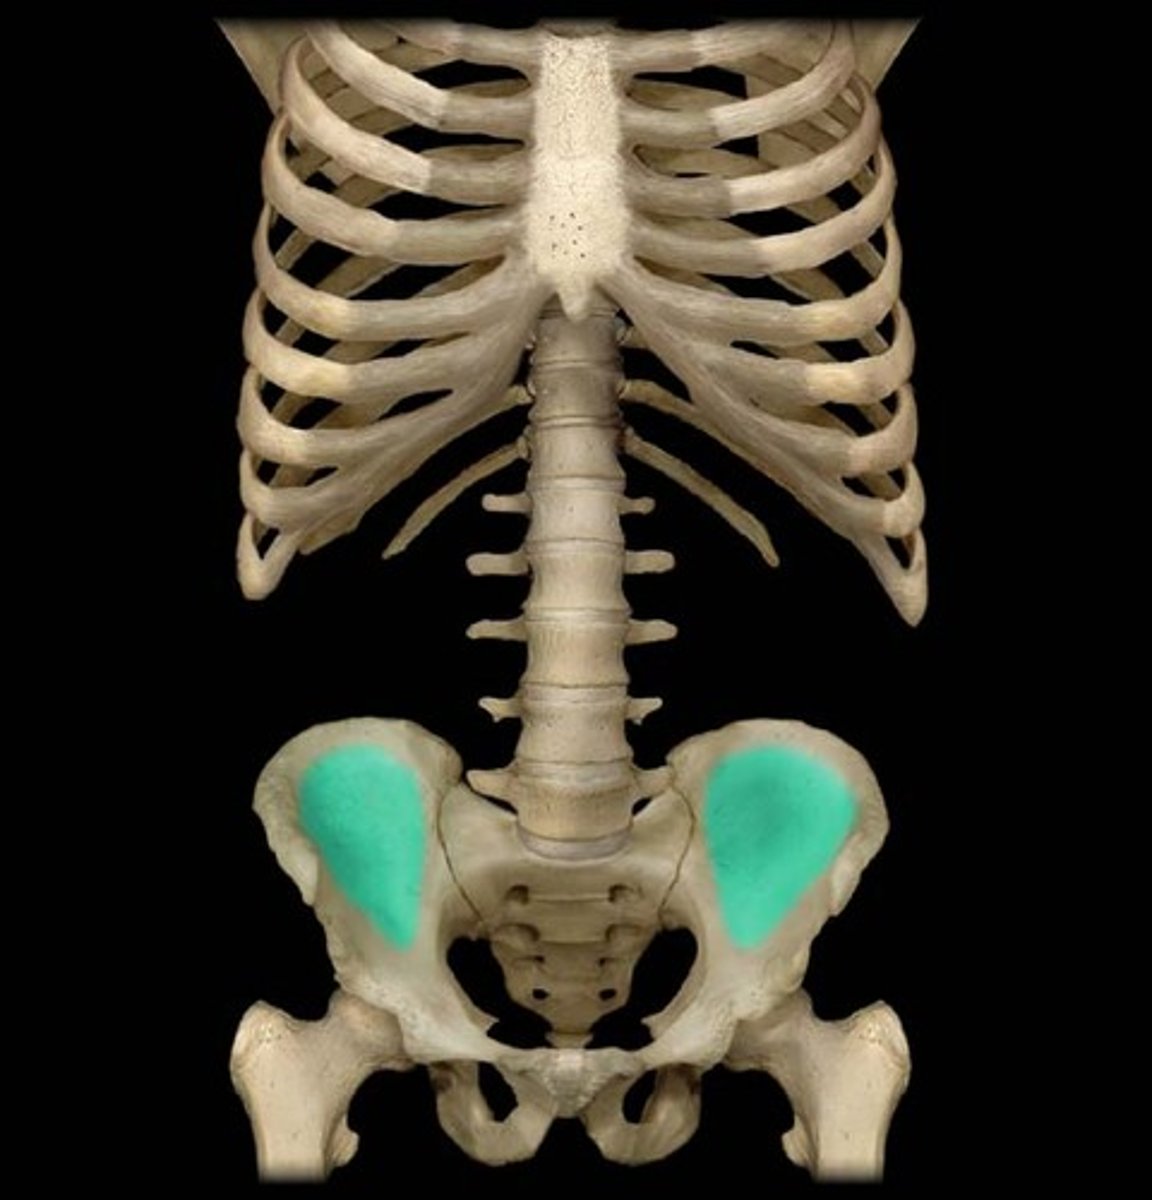

What is the term of the bones highlighted in green?

Iliac Fossa